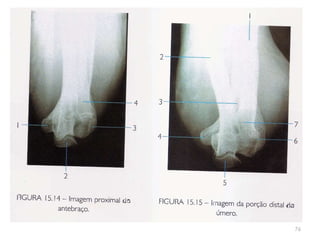

antebraço80

Incidência AP/PA do antebraço81

82

83

Incidência lateral do antebraço: látero-medial84

85

86